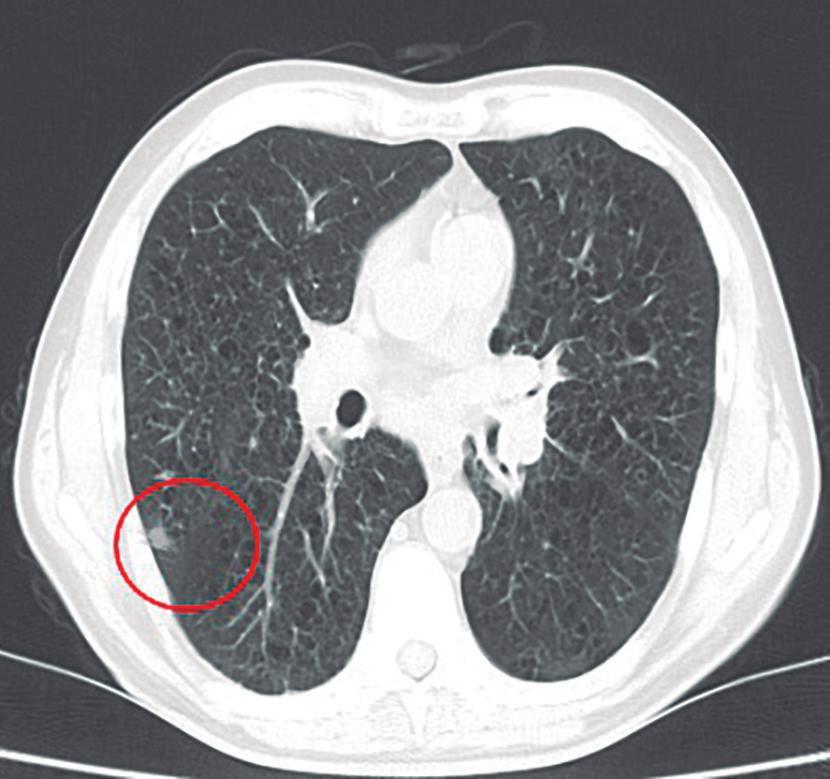

Evaluación de un paciente con dolor epigástrico y hallazgos sincrónicos infrecuentes

Roy López Grove, Daniela Soloaga, Juan Carlos Spina

Roy López Grove, Daniela Soloaga, Juan Carlos Spina 398